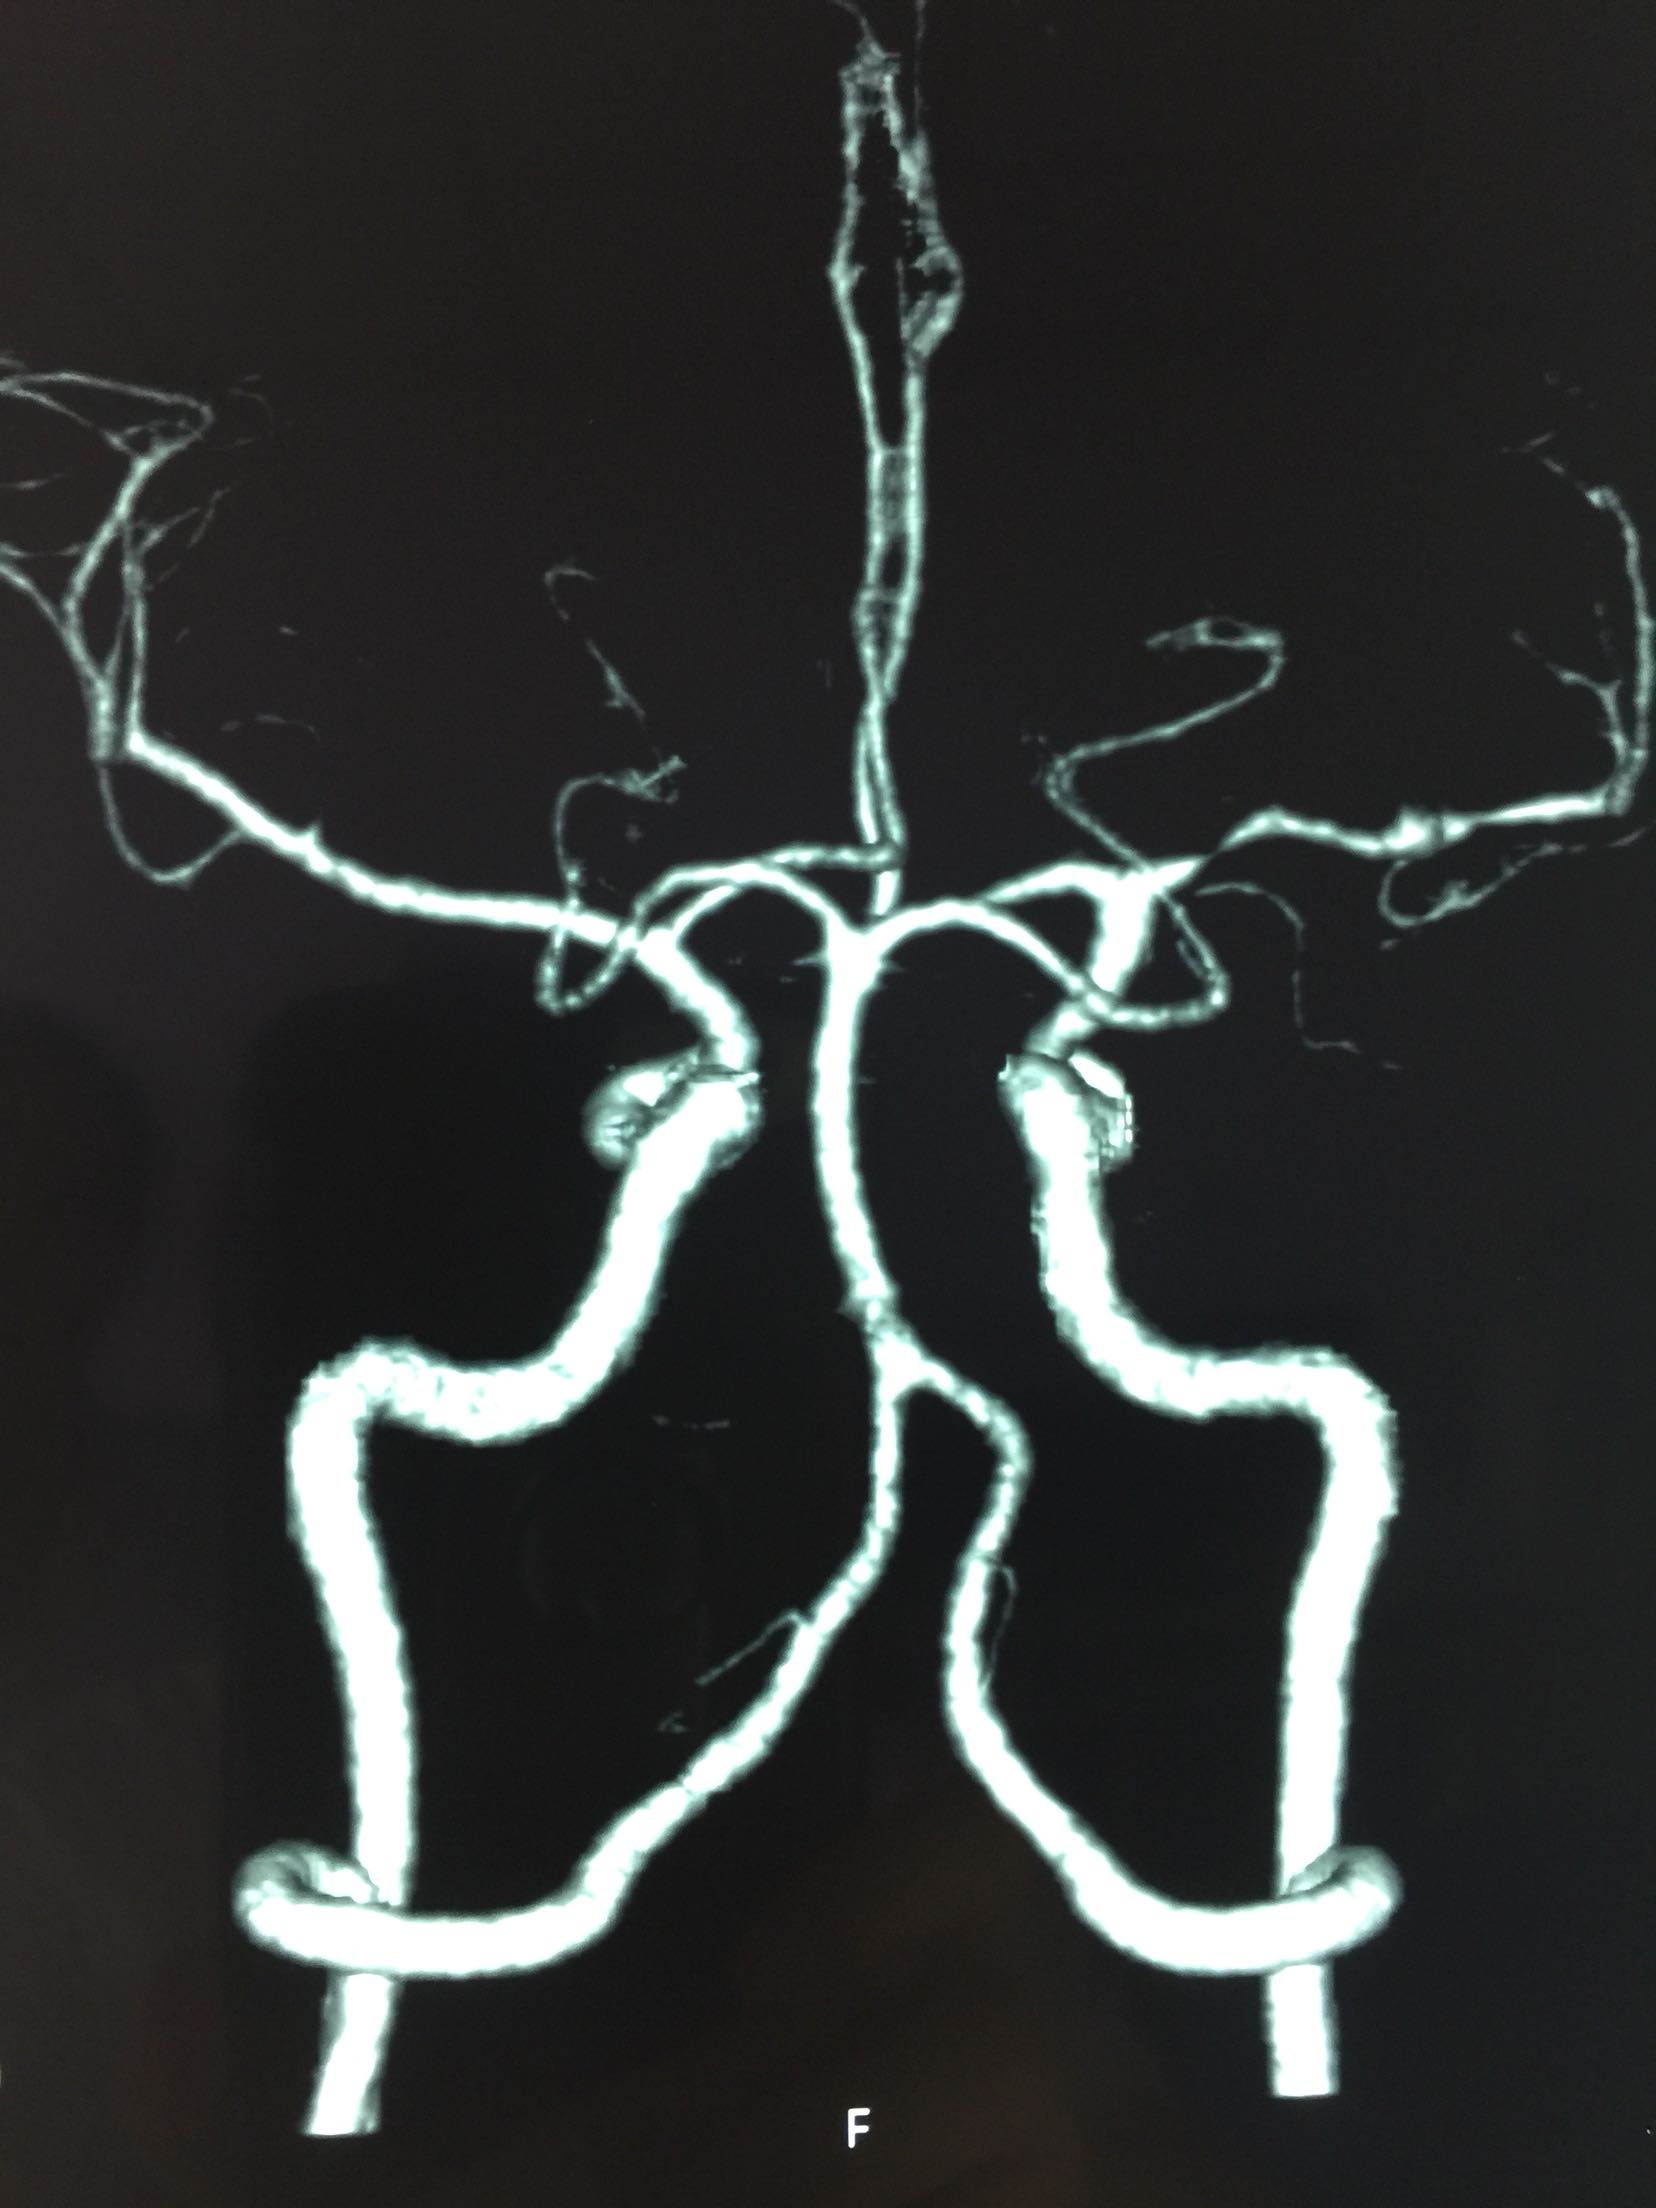

脑梗死 左侧大脑中动脉M1段狭窄

查体:T:36.5℃ P:68次/分 R:18次/分 Bp:120/70mmHg 内科系统:正常 神经系统:神志清楚,言语欠流利,查体合作,平车推人病房。左侧鼻唇沟浅,伸舌左偏,左侧肢体肌力0级,左侧肢体腱反射消失,左巴士征阳性。 辅助检查:血尿常规:正常 肝功、生化:正常 LDL-ch:5.12mmoL/l 心电图:窦性心律 头MRI+MRA、头CTA:

见下图

诊断:脑梗死 右侧大脑中动脉M1段重度狭窄 治疗:阿替普酶溶栓 醒脑静营养神经 长春西汀改善循环 丁苯肽建立侧枝循环 24小时后阿司匹林 氯比格雷抗血小板 瑞舒伐他汀降脂稳定斑块